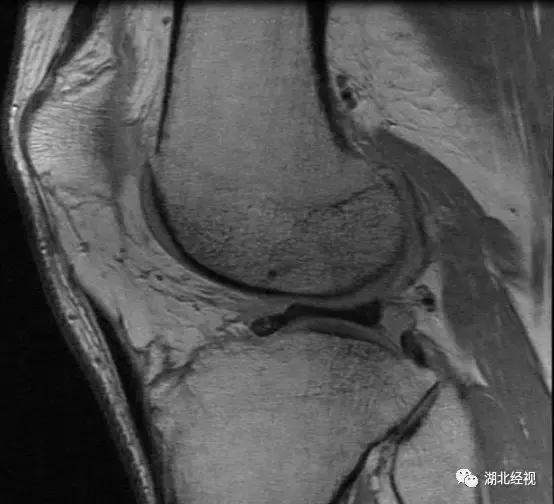

23岁的王小姐59公斤体重,160的身高。为了让自己身材看起来更苗条,她每天跑步三小时,不料膝关节闹起“*工罢**”:近两月来跑步时左膝关节总是莫名的疼痛,感觉有力使不出来,有时还有异常弹响。到医院一检查,确诊为左膝外侧盘状半月板并III度损伤。

像王小姐这样的可不在少数,医生表示,这两年随着“汉马”和夜跑族的兴起,盘状半月板患者越来越多。